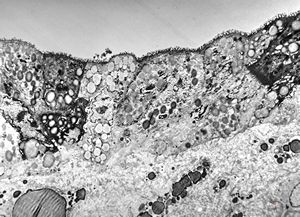

celiakia … reduced microvilli, lipid droplets